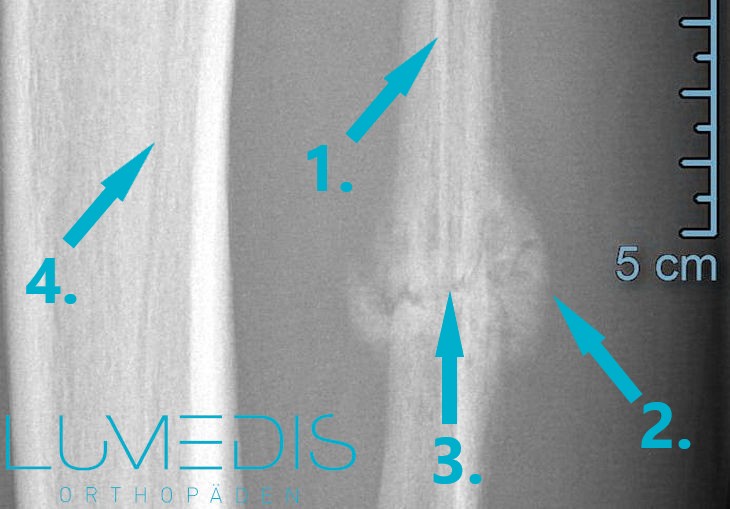

MRT eines Ermüdungsbruchs im Schienbein

Abbildung eines gebrochenen Schienbeins (angebrochen, geschlossen, offen)

Ermüdungsfraktur im Schienbein